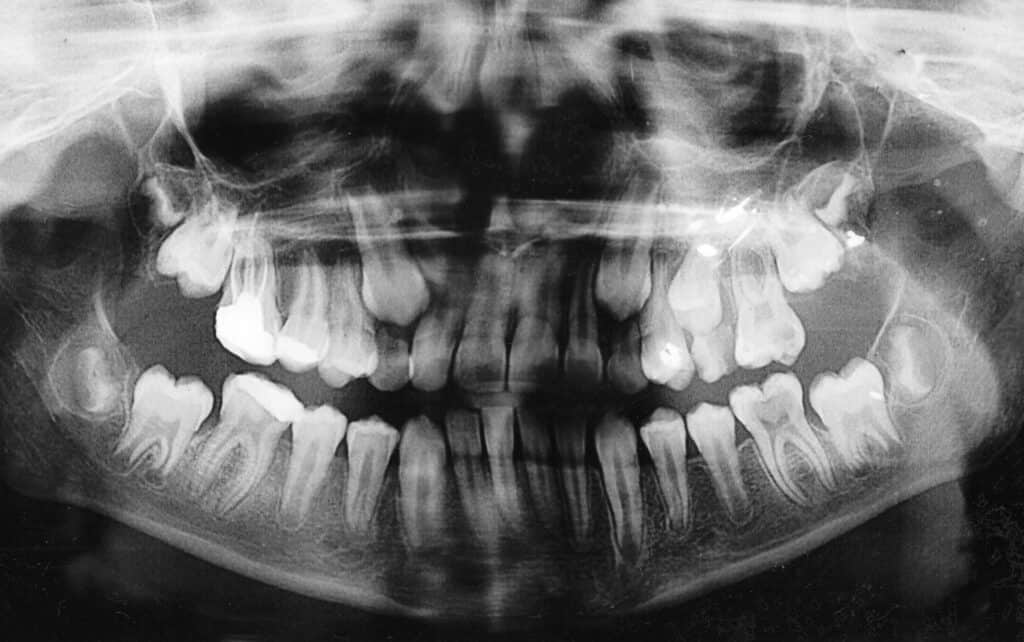

Orthopantomogram of a 12-year-old child. The upper canines and second molars have erupted while the first teeth are still in place. Why Treatment is Essential

Impacted canines are upper teeth (typically the cuspids) that fail to erupt fully into the mouth due to crowding, abnormal positioning, or other factors. Canines are crucial for maintaining alignment, supporting the structure of the mouth, and aiding in chewing. Left untreated, impacted canines can disrupt surrounding teeth, affect bite balance, and lead to further complications.